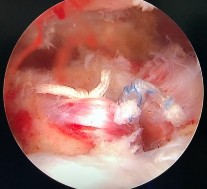

Hình phụ lục 2C: Hình ảnh xác định vị trí đặt 02 neo. (Nguồn: BN nghiên cứu)